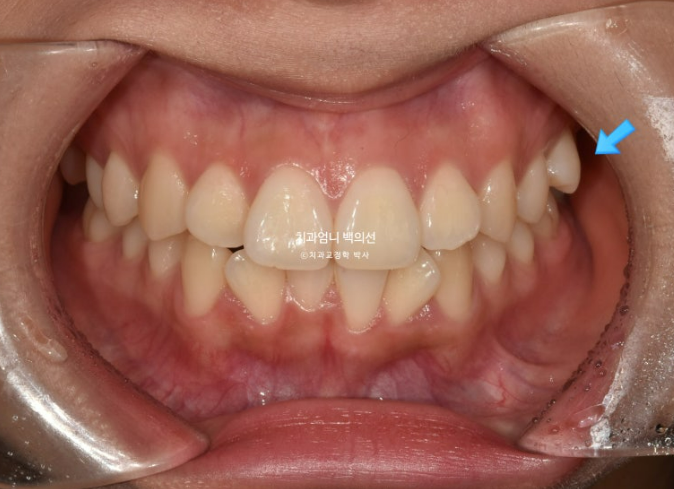

23년 12월 앞니 부분교정을 위해 오신 분입니다.

앞니 두 개가 크기도 하고 내려와 있습니다.

파란 화살표에 작은 어금니 덧니도 보입니다.

아래 앞니가 많이 삐뚭니다.

어금니 교합이 그리 좋은 편은 아니지만 환자분은 씹는데 불편함을 못 느끼는 상태였고 앞니 배열만 원하셨습니다.